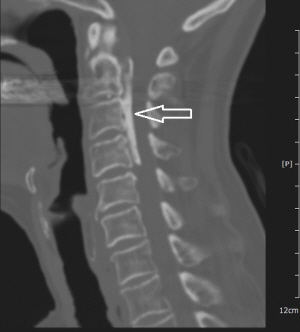

후종인대골화증 CT 사진

후종인대골화증은 X-레이, 컴퓨터단층촬영(CT), 자기공명영상(MRI) 등으로 진단할 수 있다. 발생 초기에는 안정을 취하고 약물 처방, 목보조기 착용 등 보존적 치료를 실시한다.